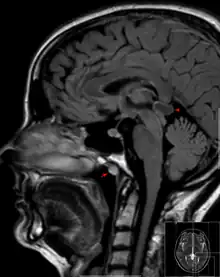

Tornwaldt cyst imaged on sagittal MRI (FLAIR). The cyst appears hyperintense in the midline of the nasopharynx (arrow). In this case there is also a cyst of the pinealis gland (arrowhead) showing a signal intensity slightly higher than the CSF. | |

A Tornwaldt cyst also spelt as Thornwaldt or Thornwald cyst[1] is a benign cyst located in the upper posterior nasopharynx. It was first described by Gustav Ludwig Tornwaldt. It can be seen on computed tomography (CT) or magnetic resonance imaging (MRI) of the head as a well-circumscribed round mass lying in the midline. In most cases, treatment is not necessary. Indications for treatment include symptomatic lesions, large lesions (>1 cm), or lesions adjacent to the eustachian tube orifice.[2]